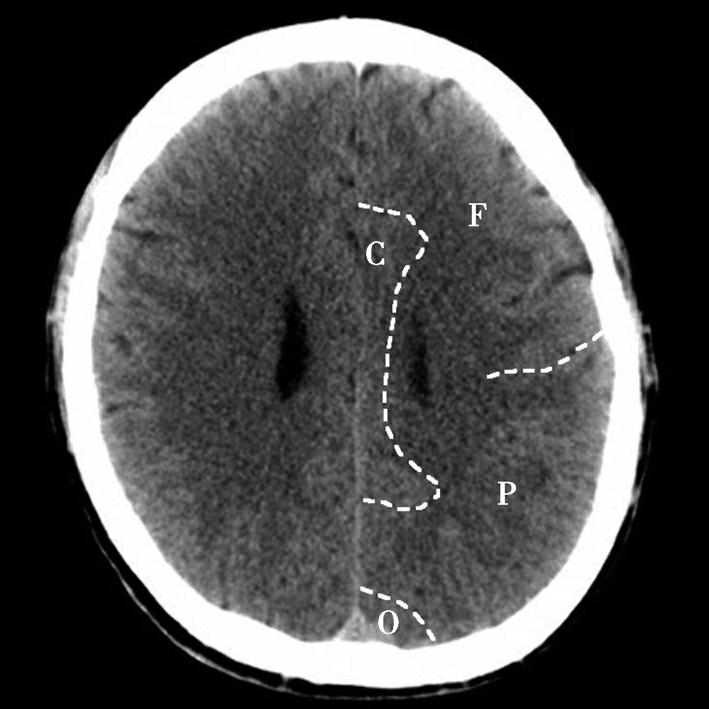

Alberta卒中项目早期CT评分(Alberta stroke program early CT score,ASPECTS)是一种评价急性缺血性卒中患者大脑中动脉供血区早期缺血性改变的简单、可靠、系统化的方法,是常用的脑卒中评定量表之一,可对缺血性病变快速进行半定量评价,有助于判定溶栓效果和远期预后。该评分主要基于CT平扫,具体分区如下(图1-2-76)所示,即选取大脑中动脉供血区2个层面。分区后共10个区域,每个区域记1分。评分时任何区域只要有低密度灶,则扣除该区域得分。正常脑ASPECTS评分为满分(10分),若MCA供血区广泛梗死累及全部区域时,则ASPECTS评分为0分。

图1-2-76 ASPECTS评分脑组织分区

A.在基底节层面(即丘脑和纹状体平面),分为各级分支M 1 、M 2 、M 3 、岛叶(缩写I)、豆状核(缩写L)、尾状核(缩写C)和内囊(缩写IC)后肢等7个区域;B.在基底节以上层面(基底节层面上2cm),包括M 4 、M 5 和M 6 。